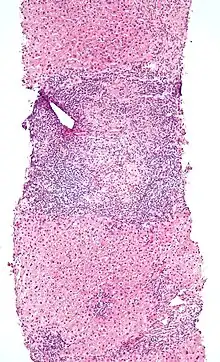

An elevated IEL population, as determined by biopsy, typically indicates ongoing inflammation within the mucosa. In diseases such as celiac sprue, IEL elevation throughout the small intestine is one of many specific markers.[1] IELs have heightened activated status that can lead to inflammatory disease such as IBD, promote cancer development and progression,[12] or become the malignant cells in enteropathy-associated T-cell lymphoma, a lymphoma that is a complication of celiac sprue.[13][14]